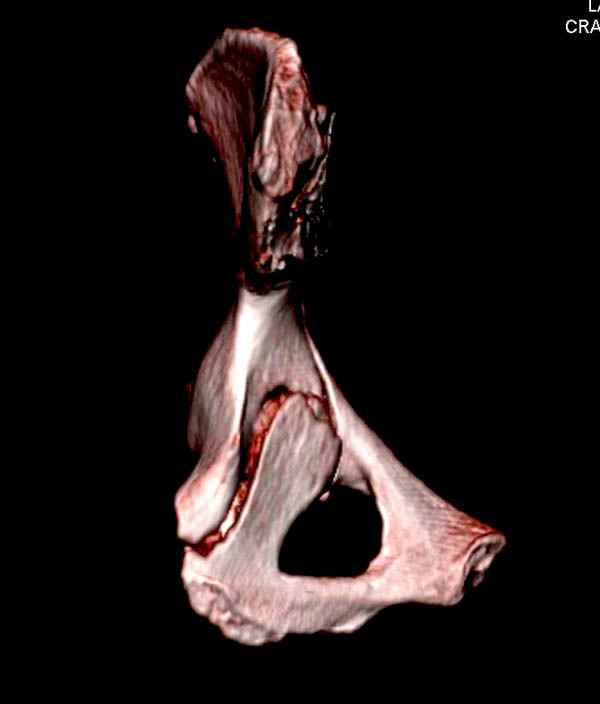

На снимке ацетабулума редко встречающийся очень низкий перелом, наверное, трудно было репозицию через один доступ? Перелом как бы замкнулся в квадрилатеральной поврехности.